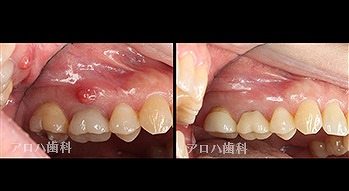

左:術前

右:術後1年

P根の穿孔封鎖

頬側の瘻孔